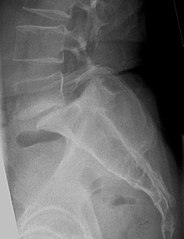

Expanding on my previous post, F# and ML.NET Regression, the current post will take a look at performing classification using Microsoft’s new ML.NET framework. The task at hand will be to use biomechanical attributes to classify patient vertebra conditions into normal (NO), disk hernia (DH), or spondilolysthesis (SL) categories.